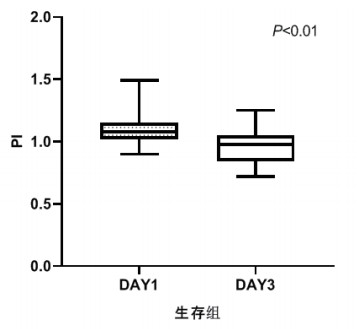

TCD参数组内治疗前后比较,生存组中无论PI还是RI在第3天时均较第1天有了明显下降,具有统计学意义(P < 0.05), 见图 2和图 3。死亡组在第1天和第3天测得的PI和RI值比较差异无统计学意义(P > 0.05),见图 4和图 5。可见生存组经治疗后脑循环较前改善,而死亡组治疗前后脑循环无明显改变。

| 图 2 生存组第1天和第3天PI比较 Fig 2 Comparison of PI between the first day and the third day in the survival group |